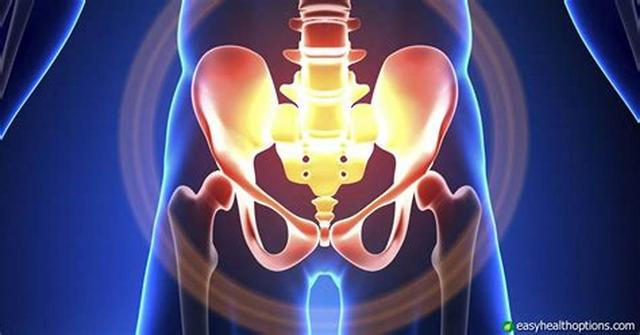

四、女性盆腔积液 。很多女性在体检的时候做彩超会发现盆腔内有少量液体存在 。 但是这都是正常的 , 在生理条件下 , 盆腔内确实存在少量液体 。

因为盆腔里面的组织也需要润滑 , 否则摩擦起来会特别疼痛 。